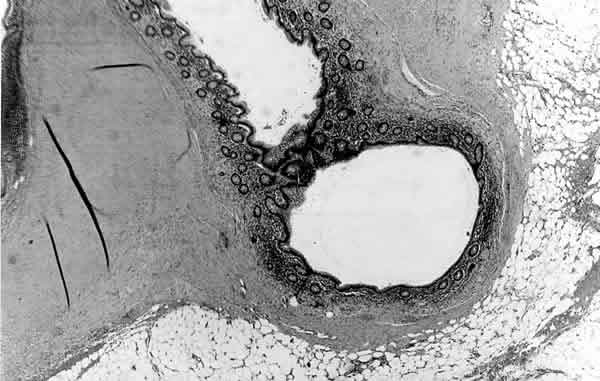

Fig. 2. 50xHE. Invaginación de la mucosa del apéndice a través de la pared, desprovista de capa muscular.